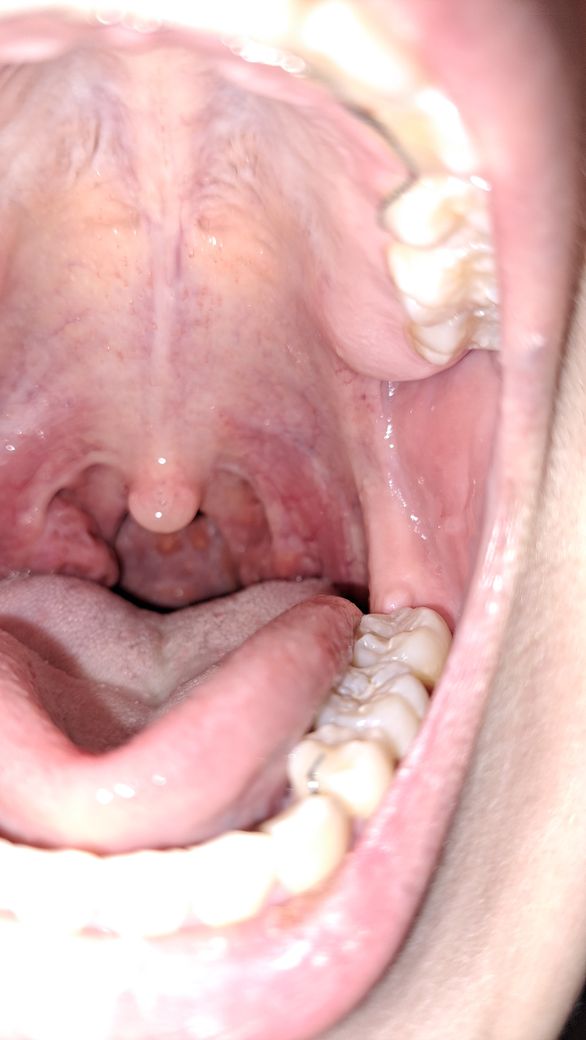

오늘아침에 양치하다 느낌이 이상해서 보니 한쪽 편도가 이렇게 커져있네요. 톡톡 건드렸을때 통증이 있지는 않습니다.

혹시 이게 단순 편도선 염증이 아니라 종양이나 혹일수도 있을까요?

현재 상태로 보았을 때는 종양보다는 편도선염일 가능성이 더 높아보이며, 이에 대한 항생제 변경 치료 또는 증상이 심할 시 수술적 절제를 고려해 봐야 겠습니다. 다만 편도암을 아예 제외시키기는 어려우므로 정확한 진단을 위해서는 근처 이비인후과에 가셔서 의사의 진료를 받아보시는 것이 좋겠습니다.

확률은 낮지만 가능성이 없다고 할 수는 없겠습니다

직접 눈으로 확인을 해봐야 합니다